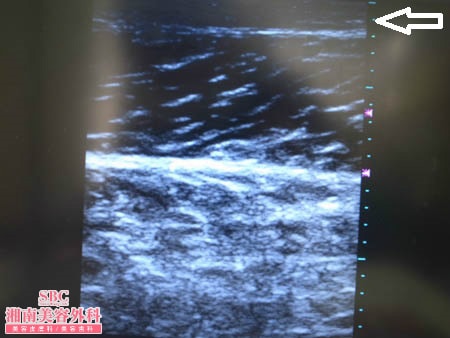

No.131077【脂肪吸引】超過激な変化!!根こそぎ竹田先生の神業ここにあり!〜他院の再手術!ふくらはぎを徹底的に細くする!左術中3Dタッチビューその1〜